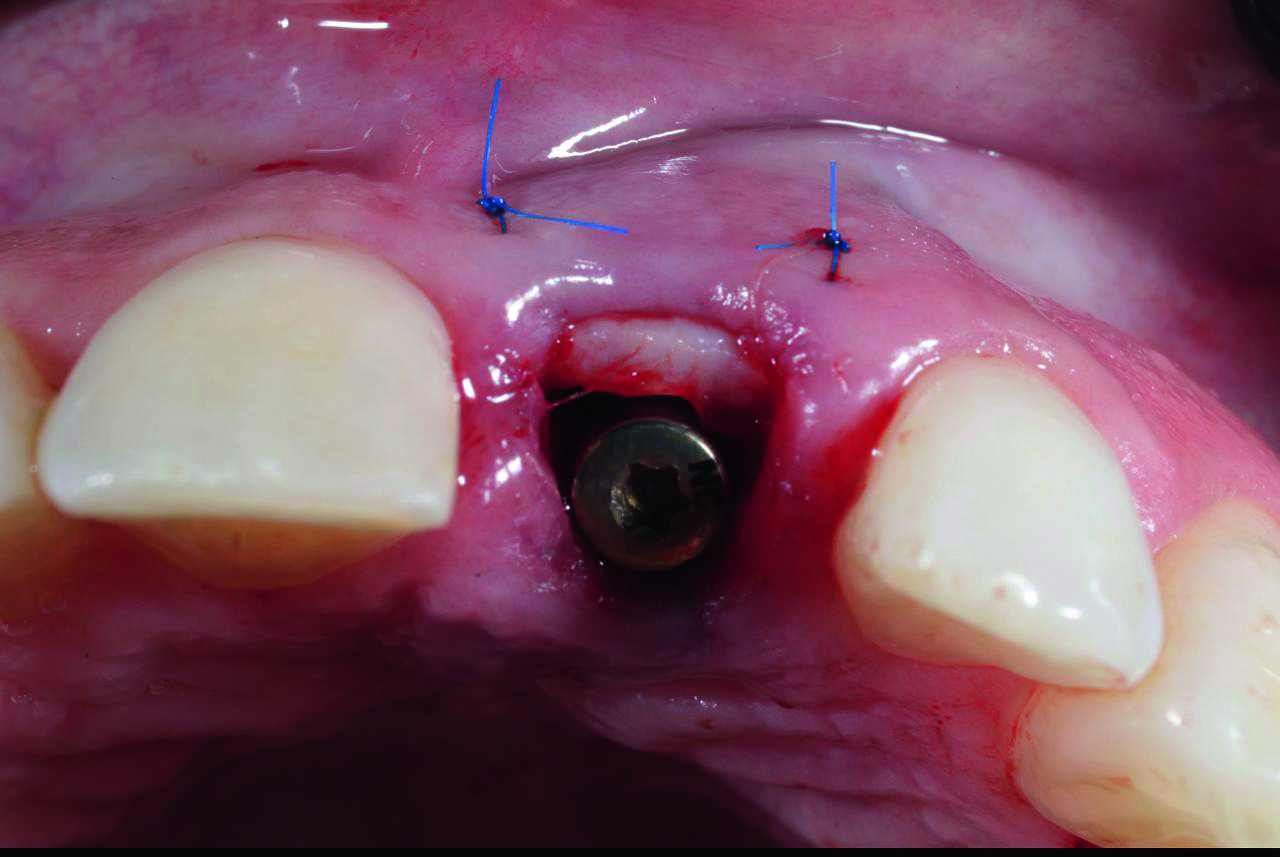

• Пластика мягких тканей в области имплантатов

• Осложнения

• Обсуждение клинических случаев